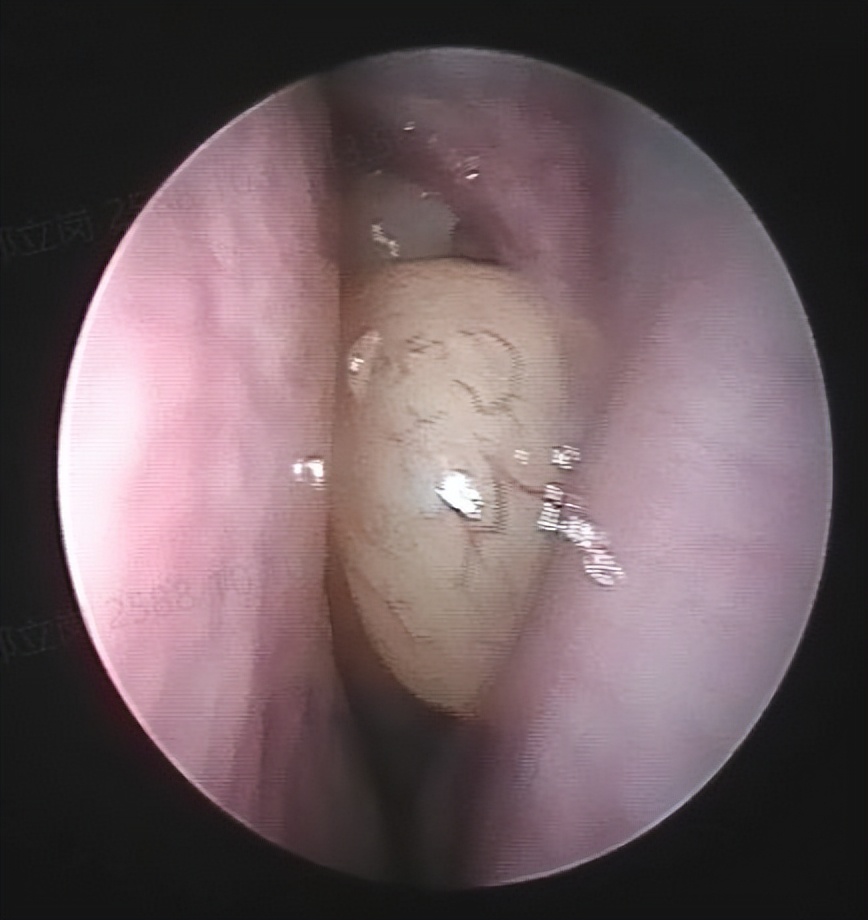

和家人商量后决定做手术治疗,就入院了。这次安排的是鼻内镜鼻窦炎微创手术和下鼻甲手术,插管全麻后就开始了手术。在鼻内镜下切除鼻息肉和开放鼻窦后,清除了炎症病变,并做了鼻甲的射频治疗,解决鼻炎的问题,整个的手术非常的顺利,用时约一个多小时。术后查房患者无明显的不适,无手术相关的并发症。